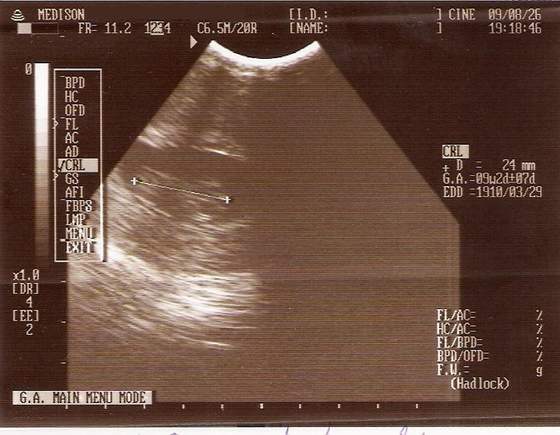

A pierwsze poczułam na uczeli idę sobie prze korytarz i takie bulgotanie poczułam i jkaby ktoś się "zamachnął", ale tak mnie wryło w podłogę, ze aż mi książki spadły.